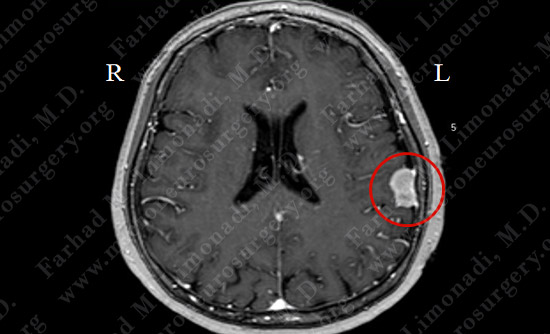

Imaging

MRI scan of the patient's brain showed a left parietal tumor arising from the dura (covering of brain).